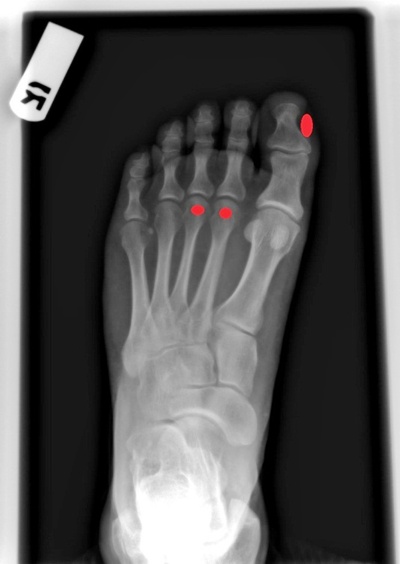

2. 발바닥 통증

평발은 발바닥 아치가 과도하게 아래로 떨어지는 움직임을 보이기 때문에 통증이 발생합니다. 특히 첫번째, 두번째, 세번째 발가락이 연결된 부위에서 통증이 나타납니다. 부산에서 평발교정 전문 치료를 받으면 이러한 통증을 효과적으로 관리할 수 있습니다.